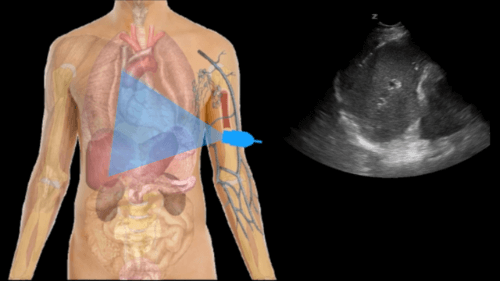

E-FAST Exam Explained Clearly – Medcram